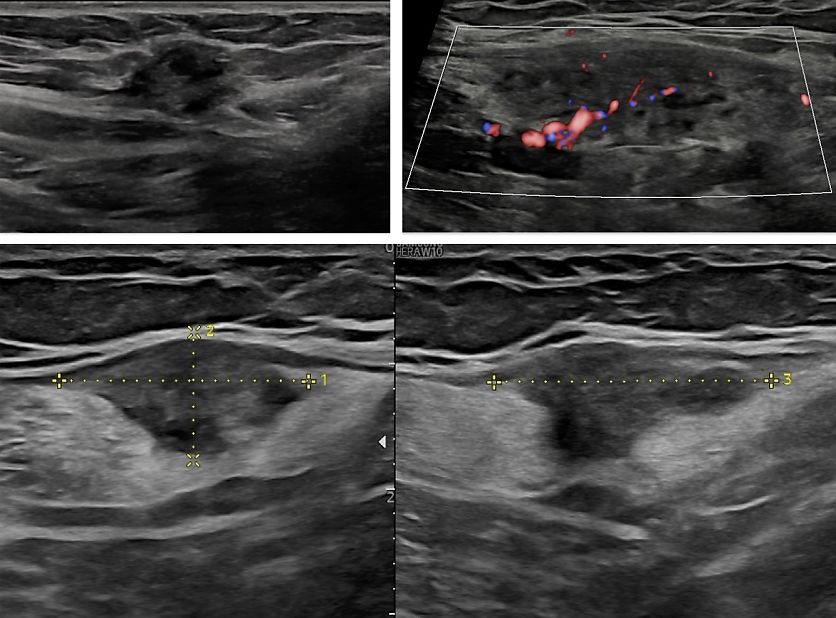

Bladder

The bladder is the most affected organ in cases of DE of the urinary tract. Lesions typically arise from the posterior bladder wall or dome (Figures 9–12), often within the detrusor layer. On TVS, these appear as hypoechoic nodules, sometimes with posterior acoustic shadowing. The lesions can be intramural or transmural, and they may protrude into the bladder lumen (Figures 10–12). Optimal bladder filling is essential for assessing wall integrity and nodule extent. The lesion should be evaluated in three orthogonal planes and its maximal dimensions should be measured, as well as the distance to the ureteral orifices if they are visible.5

Color Doppler can help distinguish between fibrotic and vascularized lesions (Figure 12). When ultrasound findings are ambiguous, or when the nodule is situated cranially, transabdominal ultrasound or MRI may be used as complementary tools.31,3

12

Typical appearance of a bladder endometriotic nodule: hypoechoic, irregular lesion protruding into the bladder wall. On color doppler, it shows moderate vascularization.